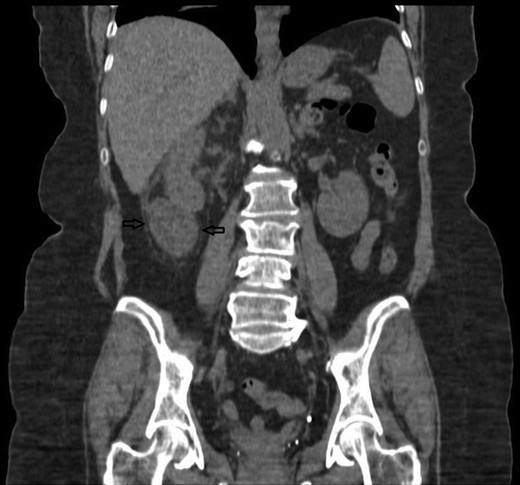

Despite intravenous antibiotics, after 72 h, the patient reported ongoing right loin pain and with persistently raised WCC at 16.6. A decision was made to proceed with a computerized tomography (CT) scan. This showed a bi-limbed right lower pole staghorn calculus measuring 29 × 16 mm associated with a 53 × 56 × 33 mm fluid collection within the right perinephric space. This was associated with inflammatory stranding abutting the lower pole in keeping with a urinoma secondary to a ruptured lower pole calyx, which was not dilated at the time of the scan (Figs 3 and 4).

A non-contrast CT coronal view, showing the right kidney with a retroperitoneal collection associated with the lower pole. The stone is anterior to this CT slice.